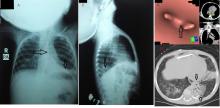

[4]Figure 2. Intraoperative images showing the VP shunt during its removal from the left lower lung lobe.

The left lower lobe of the lung was dissected from the diaphragm, which revealed the site of penetration of the VP shunt; the shunt was associated with a herniated piece of omentum. Removal of shunt from lower lobe was done first, and then the authors proceeded to a left lower lobectomy. The herniated piece of omentum was excised with repair of the diaphragm with two layers of interrupted mattress silk 2/0 sutures. A left chest drain was placed, and the thoracotomy was closed in layers in a standard fashion.